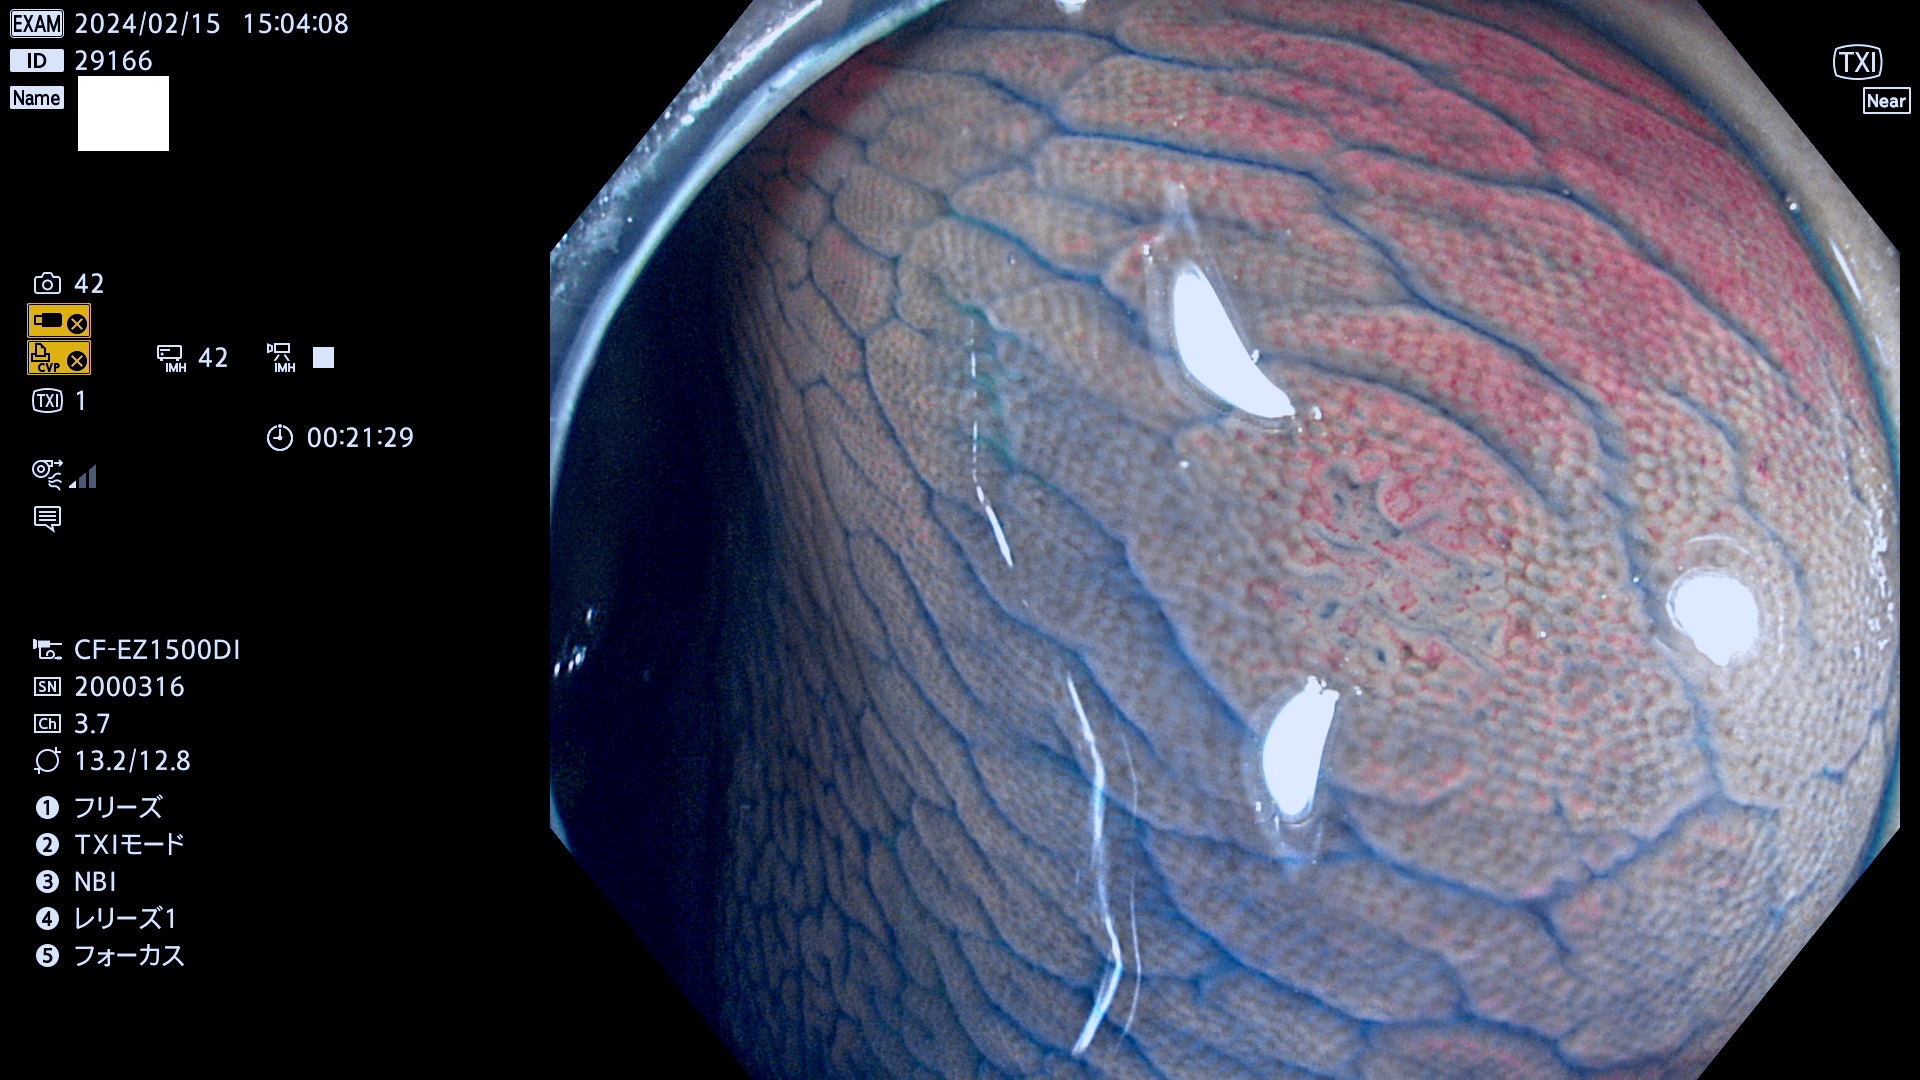

表面型腺腫(Flat Adenoma)の中で、完全に平坦な物をUb、陥凹している物をUcと呼びます。平坦隆起型(Ua)よりも、発見が難しく危険な病変です。

毎週の検査(木・金・土・日)に発見されたUb、Uc型・腺腫を、その週の日曜の夜にUPし1週間、提示します。

抽出の対象期間 2024年2月15日(木)〜2月18(日)の4日間(40件の検査)10件 (10/40=25%)